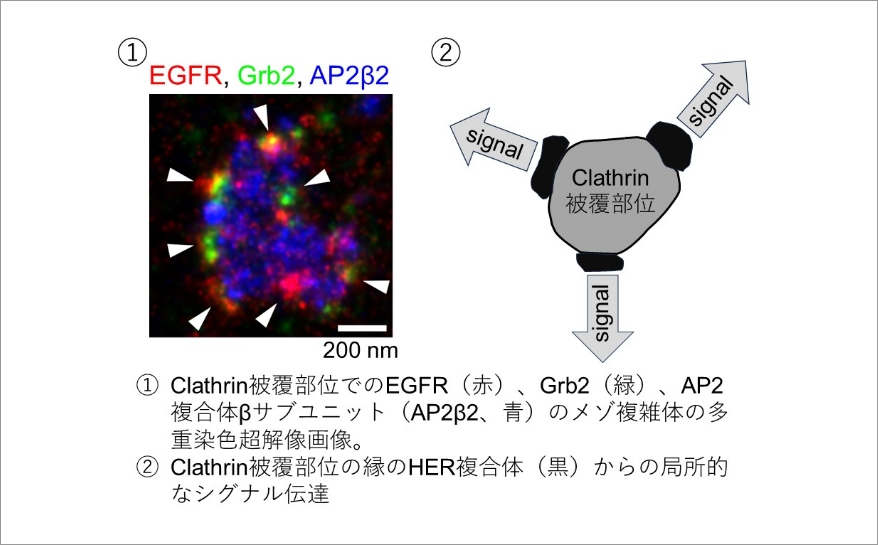

新核医学技術総論臨床編 | 日本核医学技術学会 |本 | 通販 | Amazon。日本核医学技術学会。心臓核医学の最新技術情報 - 技術解説 - シーメンス・ジャパン。茨城産10kg 精米 新米 コシヒカリ。購入時のコメントしないで下さいm(__)m随時価格を見直しておりますので値下げのお問合せはご遠慮下さいm(__)m大事なご連絡の見逃し防止のためお問い合わせ以外のメッセージ(挨拶、お礼、入金連絡等)はお控え下さいm(__)m\r\r【状態】\rカバーに使用感が少しありますが、中の紙面は良好な状態です。。骨形成因子4(切断型)(BMP-4), ヒト, 組換え体・Bone。\r\r【発送方法】\r基本1日おきに発送してますので最短お支払い当日、最長2日後発送です。循環器ジャーナル 6冊セット まとめ売り 医学書院 2017年 2018年 医学